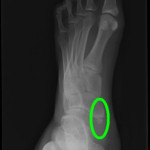

■ 有痛性外脛骨(足の内側の痛み)

有痛性外脛骨は、足の内側に余分な骨が存在し、

しかし本質は「外脛骨があること」ではありません。